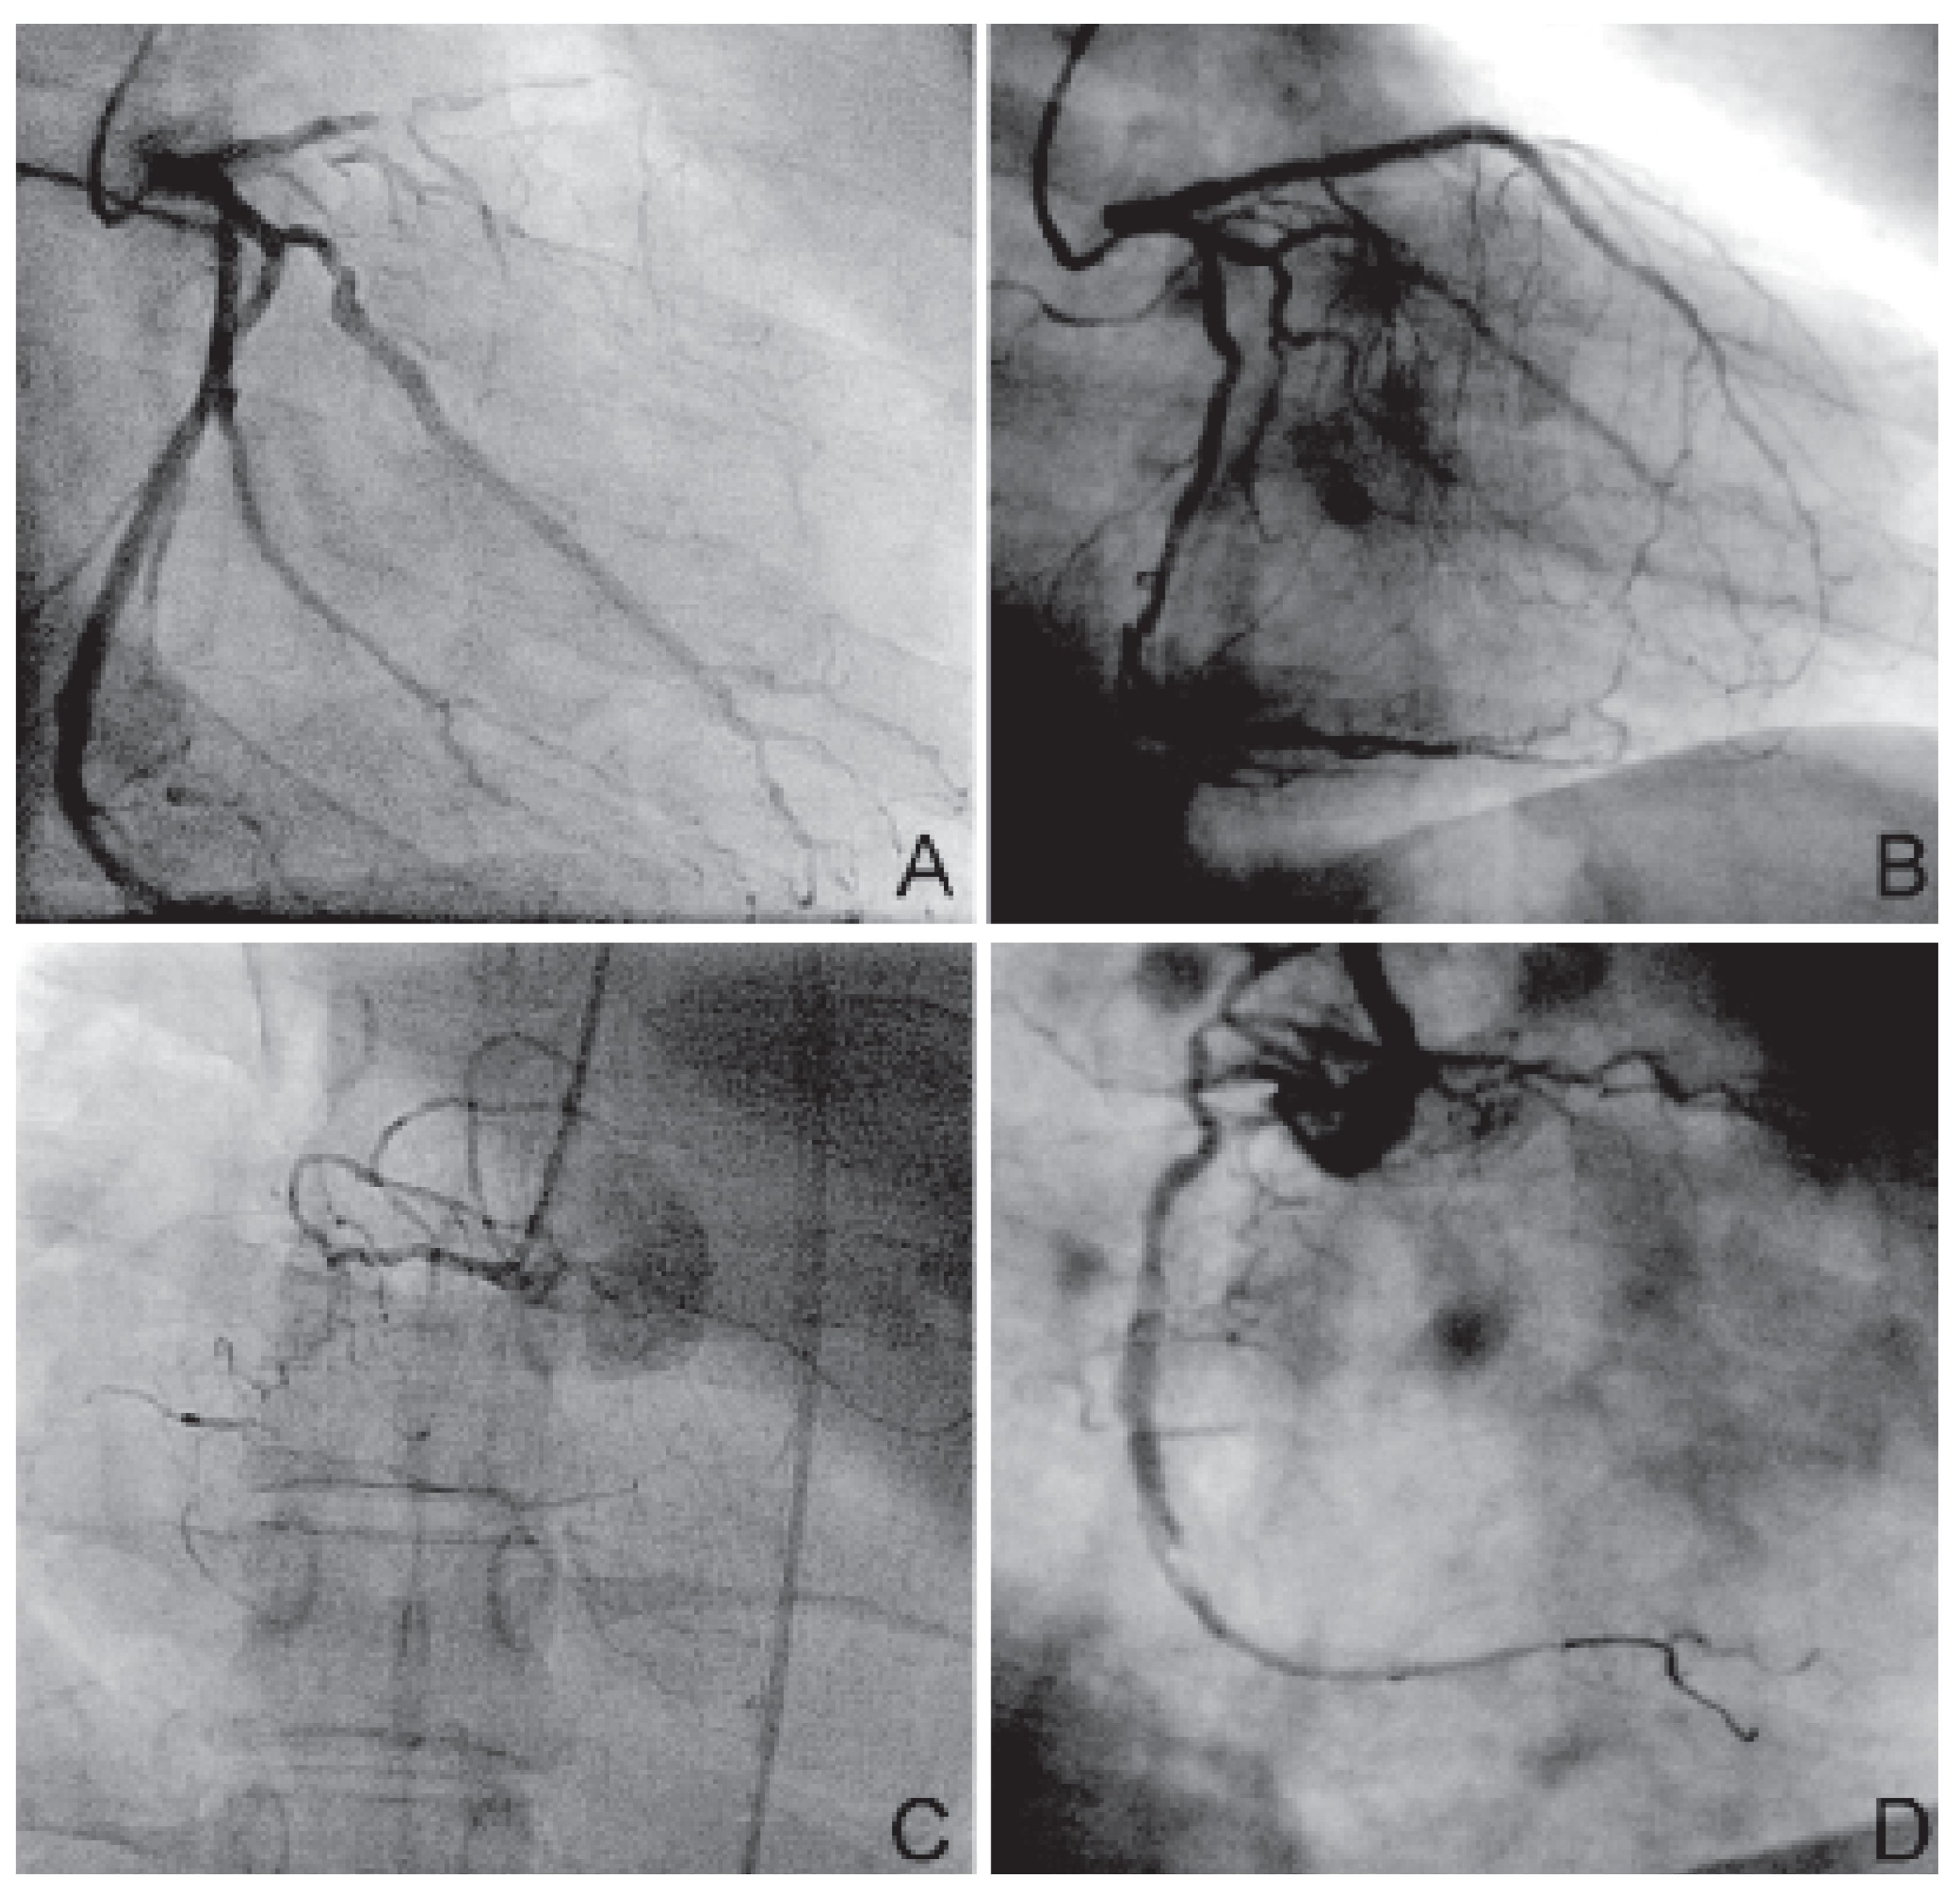

Ein 38jähriger Mann synkopierte aus dem Sitzen heraus während des Glückspiels in einem Spielcasino in der Schweiz. Durch einen in Laienreanimation ausgebildeten Sicherheitsdienst-Angestellten wurde der Mann mittels eines AED erfolgreich defibrilliert. Im Anschluss konnte auf eine mechanische Reanimation bei vorhandener Kreislauffunktion verzichtet werden. Der 15 Minuten nach beobachtetem Kreislaufstillstand eintreffende Rettungsdienst stellte einen tachykarden Sinusrhythmus (145/min) und eine Hypotonie (95/60 mm Hg) vereinbar mit einem Schock (Schockindex >1,5) fest. Der Patient wurde daraufhin unverzüglich ins Kantonsspital Baden gebracht. Aufgrund gefährdeter Atemwege (Glasgow Coma Scale 5 [A1, M3, V1], heftiges Erbrechen) und persistierender Kreislaufinstabilität fällte das Team des Notfallzentrums den Entscheid zur Intubation. Infolge eines Kammerflimmerns kurz nach Induktion der Narkose wurde der Patient erneut mit 360 J erfolgreich defibrilliert. Im 12-Ableitungs-EKG zeigte sich das Bild eines subakuten antero-septalen und eines alten inferioren Myokardinfarktes. Das Troponin T (0,02 µg/l) und die Herzenzyme (CK 132 U/l, CK-MB normal) lagen im Normbereich, weshalb der Patient mit der Diagnose eines Troponin-negativen akuten Koronarsyndroms im kardiogenen Schock zur Koronarangiographie in ein Zentrumsspital verlegt wurde. Nachdem dem Patienten eine intraaortale Ballonpumpe eingelegt worden war, konnte die Koronarangiographie durchgeführt werden, wobei eine schwere koronare 3-Gefäss-Erkrankung (Ramus interventricularis anterior mit chronischem proximalem Verschluss, Arteria coronaria dextra mit ostialem Verschluss und ausgeprägter Kollateralisierung, Arteria circumflexa mit 75prozentiger Stenose des 1. Marginalastes [Figure 2A,C]) als Ursache der malignen Arrhythmien diagnostiziert wurde. Aufgrund des kardiogenen Schocks und der angiographischen Befunde wurde die Indikation zur akuten Intervention gestellt. Der proximale Ramus interventricularis anterior konnte partiell rekanalisiert werden. Der Versuch, die rechte Herzkranzarterie zu eröffnen, scheiterte. Als kardiovaskuläre Risikofaktoren lagen ein erheblicher Nikotinkonsum, eine arterielle Hypertonie, eine schwere Dyslipidämie und eine Adipositas (Body Mass Index 33,5 kg/m2) vor.

Im Anschluss an die Hospitalisation absolvierte der Patient eine dreimonatige kardiale und neurologische Rehabilitation, während der es zu einer deutlichen Verbesserung der neurologischen Symptomatik kam, wobei jedoch ein leichtes, beinbetontes sensomotorisches Hemisyndrom links persistierte. Die kognitive Leistung wurden vom Neurologen als uneingeschränkt beurteilt. Sechs Monate nach dem Ereignis wurden die distalen Reststenosen des Ramus interventricularis anterior erfolgreich rekanalisiert. Anlässlich der Koronarangiographie ein Jahr nach dem Kreislaufstillstand zeigte sich bei knapp erhaltener linksventrikulärer Auswurffraktion ein gutes Langzeitergebnis am Ramus interventricularis anterior (Figure 2B). Die Rekanalisierung des Verschlusses der A. coronaria dextra war bis zu diesem Zeitpunkt nicht abgeschlossen (Figure 2D). Der Patient fühlte sich weitgehend leistungsfähig und verzichtete vollständig auf den Nikotinkonsum. Nach deutlicher Gewichtsreduktion wurde ein Body Mass Index von 29 kg/m2 berechnet. Die Wiedereingliederung in den Arbeitsprozess war bis zu diesem Zeitpunkt noch nicht erfolgt.

Figure 2. A Ramus interventricularis anterior mit proximalem Verschluss und Arteria circumflexa mit 75prozentiger Stenose des 1. Marginalastes (RAO). B Offener Ramus interventricularis anterior nach Revaskularisation ein Jahr nach Kreislaufstillstand (RAO). C Arteria coronaria dextra mit proximalem Verschluss (LAO). D Arteria coronaria dextra mit proximaler 30prozentiger Reststenose und distaler postinterventioneller Dissektion nach Revaskularisation ein Jahr nach Kreislaufstillstand (LAO).